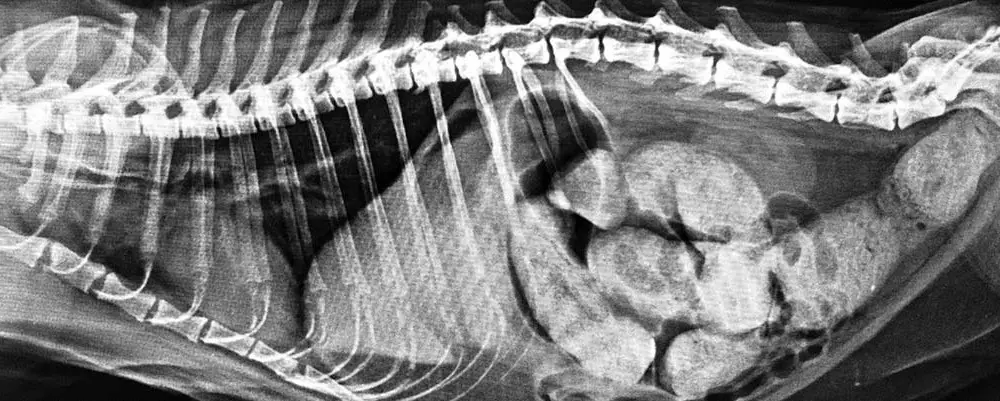

DIAGNOSTYKA